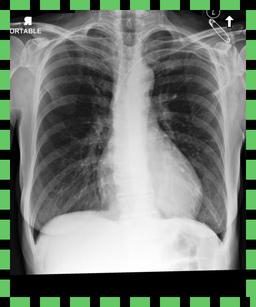

In this regard, VLP in biomedicine and radiology poses a distinctive challenge, as reports routinely include comparisons to prior imaging studies [47, 3, 57]. Without knowledge of this prior image111In the MIMIC-CXR v2 dataset [36], around 40% of reports explicitly reference a previous image. See Appendix B for details., temporal information in the text modality, e.g. “Pneumonia is improving”, could pertain to any image containing “Pneumonia”, producing ambiguity during contrastive training (Figure 1). Despite this, the existing VLP work to date considers alignment between only single images and reports [81, 32, 46, 9], going so far as to remove temporal content from reports in training data to prevent ‘hallucinations’ in downstream report generation[54]. However, temporal information can provide complementary self-supervision, solely by exploiting existing structure, and without requiring any additional data.

Table A.1 shows example reports generated with BioViL-T and BioViL models, which are compared to the reference radiologist’s reports. In comparison with BioViL which only models the current image, BioViL-T shows the benefit from incorporating prior study information and is able to provide factually more accurate reports especially in terms of describing temporal progression of the findings. This is showcased in the first two examples in the table: In the first row, BioViL-T is able to comment on not only the presence of the pleural effusion but also its improvement while BioViL fails to mention the change. In the second example, BioViL-T is able to correctly identify that there is no relevant change by comparing with the previous study, while BioViL wrongly hallucinates the tube in the current image as a new placement. BioViL-T can also avoid hallucination of the temporal information when there is no prior study. For instance, in the third example, BioViL-T correctly acknowledges that there is no prior image and generates the report based on information from the single current image, while BioViL hallucinates a non-exisistent prior study and wrongly generates temporal descriptions in the report.